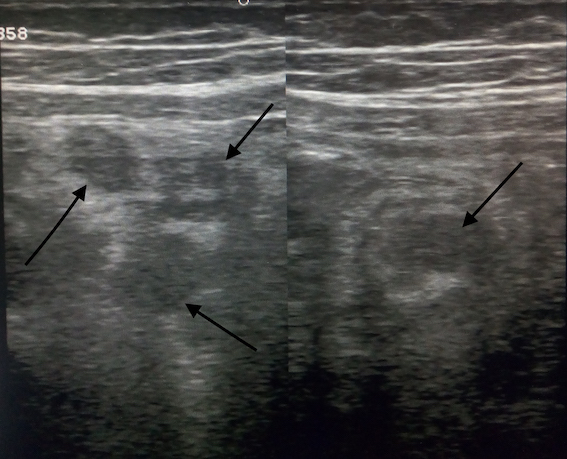

I dati di imaging sono riportati nella Tabella IV. La polmonite interstiziale postero-basale subpleurica è stato il reperto TC di maggiore riscontro (55% dei casi). Cinque pazienti hanno presentato versamento peritoneale associato o meno a linfoadenite mesenterica ed epatosplenomegalia. L’ecocardiogramma è stato eseguito in tutti i bambini, con evidenza di versamento pericardico nel 22% dei casi, insufficienza mitralica nel 33% e insufficienza tricuspidalica nel 22%. In un paziente è stato rilevato un aumento della birifrangenza coronarica. In nessun paziente è stata descritta una riduzione della frazione di eiezione. La cardio-RM è stata eseguita in post-dimissione nei 2 pazienti che hanno presentato bradicardia sinusale: in entrambi è stata confermata una funzione sistolica nella norma, in assenza di segni indicativi di edema e/o fibrosi del miocardio. La RM encefalo è stata eseguita in un paziente con sintomi neurologici, rilevando la presenza di lesioni compatibili con encefalomielite acuta disseminata (ADEM).

In accordo ai criteri diagnostici elencati in Tabella I, la diagnosi di MIS-C richiede la presenza del coinvolgimento di almeno 2 o più organi; gli esami strumentali svolgono quindi un ruolo fondamentale, soprattutto nel caso in cui l’interessamento d’organo sia clinicamente silente. Attualmente sono scarse le evidenze in letteratura riguardanti gli aspetti radiologici dei pazienti con MIS-C. I reperti toracici più frequentemente riportati sono la cardiomegalia, il coinvolgimento polmonare con aspetto a vetro smerigliato bilateralmente più o meno associato a consolidamento parenchimale (come osservato in 5 dei nostri pazienti - Figura 1), il versamento pleurico (presente anche in 4 dei nostri bambini), l’edema polmonare, l’embolia polmonare, il versamento pericardico (evidenziato altresì in 2 dei nostri bambini)13,14. Nei pazienti con MIS-C, l’imaging cardiaco (ecocardiografia e RM) può mostrare una ridotta frazione di eiezione del ventricolo sinistro, miocardite, pancardite, cardiomiopatia dilatativa e versamento pericardico15; un dato di rilievo nella nostra casistica è stato il riscontro di valvulopatia in 5 dei nostri pazienti (55%): abbiamo riscontrato 2 casi di insufficienza tricuspidalica e 3 di insufficienza mitralica, tutte di natura transitoria. Tra i reperti radiologici extratoracici, i riscontri più frequenti sono stati la linfoadenopatia mesenterica (rilevata in 2 dei nostri pazienti - Figura 2), l’ispessimento della parete intestinale con interessamento dell’ileo terminale e del cieco, l’epatomegalia, l’edema peri-portale (osservato anche in un nostro caso), l’edema della colecisti (come in uno dei nostri pazienti), i reni iperecogeni e gli infarti splenici15. La RM cerebrale nei pazienti con MIS-C può rilevare: ictus ischemico, encefalite, ADEM (rilevata anche nella nostra casistica - Figura 3) o leucoencefalite emorragica acuta15.